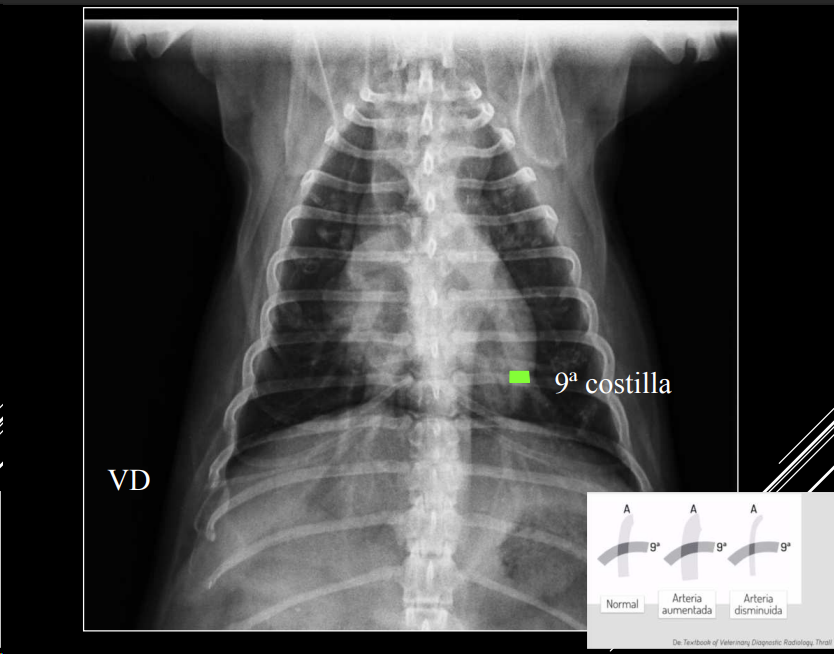

PATRÓN VASCULAR

- Cambios en tamaño, densidad o forma de vasos.

- Arteria y vena lobulares craneales del mismo tamaño.

- Comparación: grosor ≈ 4ª costilla (LL) o 9ª costilla (VD).

- Hipervascular o hipovascular.

- Posible mineralización (uremia, filariosis).

- Tortuosidad o cortes bruscos en arterias pulmonares → filariosis.